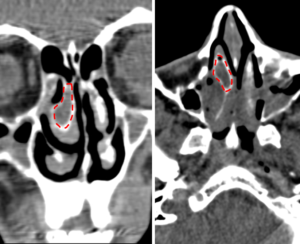

Буллезная деформация средней или нижней носовой раковины встречается достаточно часто, но редко диагностируется. Это состояние чаще всего сопровождает хронический гипертрофический или аллергический ринит и не выявляется при обычных методах осмотра.

Буллезная трансформация средней носовой раковины — образование в толще слизистой оболочки носа воздушного пузырька — буллы. Гистологически, эти образования не являются кистой, так как заполнено воздухом, а не жидкостью.

Компьютерная томография, стрелкой указана воздухоносная полость (булла) в средней носовой раковине